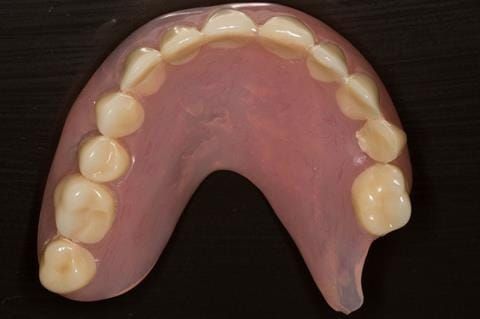

- Cobalt chromium reinforced gasket denture - using a Molloplast B "O" ring to retain and stabilise the denture. This was my professional preference as this was the least invasive and simplest solution to this dental problem. Should the UR7 require removal in the future - an artificial tooth could be added - resulting in a complete denture. The patient would have adapted to the denture fully by this stage and have good neuromuscular control of the prosthesis.

Following consultation and second discussion appointment the patient chose to have option 2 namely, a window denture - maxillary cobalt chromium based partial denture. The clinical situation and treatment process is shown in detail below with photographs. The patient was successfully rehabilitated with this and her quality of life considerably improved. The clinical work was provided by Finlay and the technical work by Rowan.